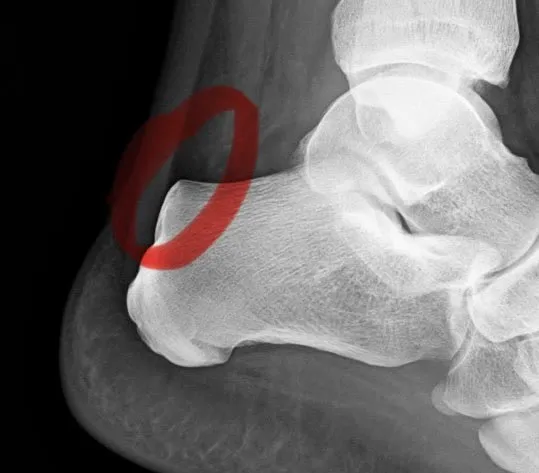

Diagnose Haglundferse und damit das (vorläufige) Ende des Wettkampfsports. Laufumfänge und -intensität auf ein Minimum reduziert. Und zurück zu den Wurzeln. Bin jetzt wieder Multisportler: Mehr Radfahren, mehr Schwimmen, mehr Tennis, mehr Ski, mehr Krafttraining, …